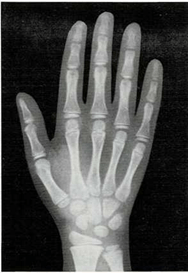

Mi madre me respondió: “Una razón de que lo encuentres blando es que sus huesos no son tan duros como los tuyos. Los niños, al nacer, tienen muy pocos huesos duros. Los huesos de su esqueleto se componen sobre todo de cartílago. Pero las células óseas trabajan sin descanso, y por ello sus huesos crecen y se endurecen muy deprisa. Tus huesos son más largos y duros que los del niño. Los huesos seguirán creciendo y se endurecerán hasta tus veinte años.

El médico me respondió: “Tu muñeca tiene ocho huesos. Pero no todos crecen a la vez. Los huesos de la muñeca de algunos niños crecen más deprisa o más despacio que los de otros niños. Pero los huesos de la muñeca crecen a un mismo ritmo en todos los niños sanos. Si los huesos de tu muñeca salen bien en la radiografía, quiere decir que el resto de los huesos de tu cuerpo también están bien.”

En ella ya se ven claramente los ocho huesos.